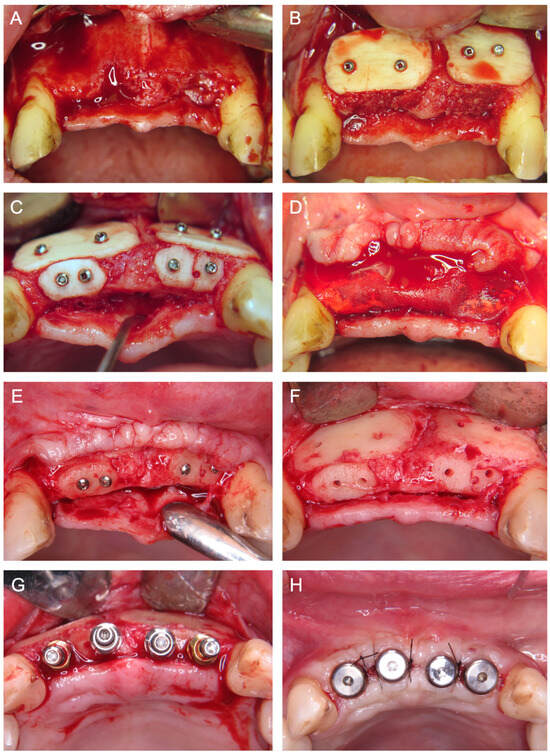

- CAD/CAM TM—Customized CAD/CAM-manufactured titanium mesh (Yxoss CBR®; ReOss GmbH, Filderstadt, Germany), designed from CBCT data and filled with autogenous bone chips, allogeneic granules (maxgraft® granules; botiss), and/or bovine BS (±hyaluronic acid), and fixed with titanium screws (Figure 5).